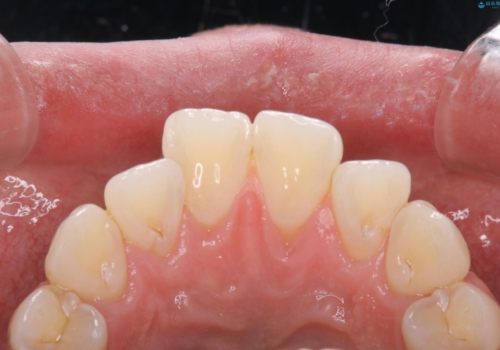

PMTCを初めてやったとのことで、全体的にステイン、プラーク、歯石が多く付着していました。これから虫歯の治療や矯正がスタートするため、歯茎が腫れていたり、汚れが付着していると、虫歯や歯周病が進行してしまうため、治療と並行してブラッシング指導、クリーニングを行っています。何よりも日々のクリーニング(ホームケア)が大切なため、頑張っています。